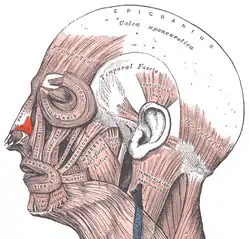

- Nasal muscles – The movements of the human nose are controlled by groups of facial and neck muscles that are set deep to the skin; they are in four functional groups that are interconnected by the nasal superficial aponeurosis—the superficial musculoaponeurotic system (SMAS)—which is a sheet of dense, fibrous, collagenous connective tissue that covers, invests, and forms the terminations of the muscles.

The movements of the nose are affected by

- the elevator muscle group – which includes the procerus muscle and the levator labii superioris alaeque nasi muscle.

- the depressor muscle group – which includes the alar nasalis muscle and the depressor septi nasi muscle.

- the compressor muscle group – which includes the transverse nasalis muscle.

- the dilator muscle group – which includes the dilator naris muscle that expands the nostrils; it is in two parts: (i) the dilator nasi anterior muscle, and (ii) the dilator nasi posterior muscle.